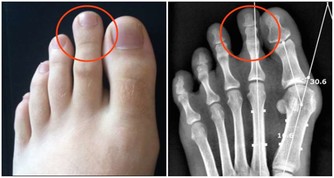

氣溫驟降時,腦血管疾病發病者明顯增加。劉霞發病時,正好遇到兩大誘因,一是天氣轉冷,二是深夜用熱水泡腳,都可能令血管受到強烈刺激,一定程度上誘發疾病。因此,有腦血管基礎性疾病的市民,近期應注意防寒保暖,避免身體遭受冷暖刺激。少用過熱的水洗澡、泡腳,少喝酒,避免情緒激動。同時,還應定時對身體進行全面檢查。

這類病人泡腳時要格外小心,一是水溫不可過高,二是泡腳時間不能過長,因為用熱水泡腳后,會迅速導致人體血管擴張,全身血液會由重要臟器流向體表,因此很容易使心臟、大腦等重要器官缺血缺氧,因此對於有心臟病、低血壓的人群來說,就會增加他們發病的危險。